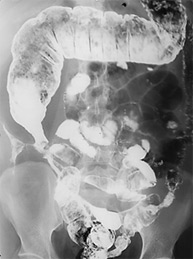

Болезнь Крона тонкой кишки,

осложненная межкишечными свищами.

|